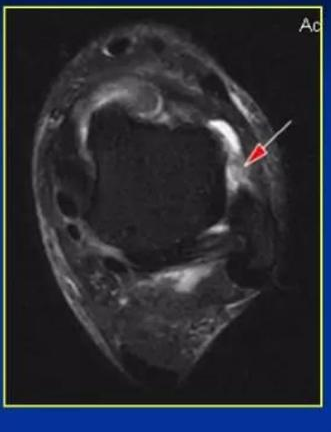

磁共振提示距腓前韧带断裂

关节镜观察断裂的距腓前韧带